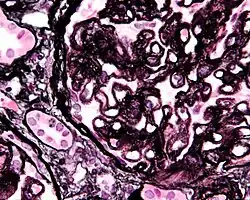

Micrograph showing glomular basement membrane spike formation in membranous nephropathy. Jones stain.

The glomerular basement membrane of the kidney is the basal lamina layer of the glomerulus. The glomerular endothelial cells, the glomerular basement membrane, and the filtration slits between the podocytes perform the filtration function of the glomerulus, separating the blood in the capillaries from the filtrate that forms in Bowman's capsule.[1] The glomerular basement membrane is a fusion of the endothelial cell and podocyte basal laminas,[2] and is the main site of restriction of water flow.[3] Glomerular basement membrane is secreted and maintained by podocyte cells.

The glomerular membrane consists of mesangial cells, modified pericytes that in other parts of the body separate capillaries from each other. The podocytes adjoining them have filtration slits of diameter 25 nm that are formed by the pseudopodia arising from them. The filtration slits are covered by a diaphragm that includes the transmembrane protein nephrin.